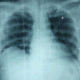

Dokter ijin bertanya, bacaan rongent di bawah

Pendapat saya kalau dari gambar yang dokter lampirkan:

Trakea masih lurus di tengah, tulang juga tidak tampak fraktur.

Kemudian untuk cor mungkin ada kardiomegali dok

Paru: corakan bronkovaskular meningkat dan ada infiltrat di paru kanan.

Diafragma meninggi, tapi sudut costofrenikus kayanya masih lancip dok.

Kalau boleh tau klinis pasien bagaimana ya dok? Ini foto pasien posisi apa dok? Standing atau sitting? Apakah inspirasi maksimal?

CMIIW, Mungkin ada radiolog atau dr paru yang bisa bantu?

Kalau ada riwayat pengobatan SLE mungkin ada pneumonia dokter atau ada efusi pleura dok sebelah kanan? Mungkin bisa diminta posisi lateral atau right lateral decubitus untuk konfirmasi (karena ada peninggian diafragma di sebelah kanan).

Dengan pertimbangan pasien mengonsumsi imunosupresan dan SLE, apalagi kalau memang ada demam dok. Pengobatan SLE nya apa ya dok? Dosis steroidnya masih loading dose atau sudah rumatan dok?

Apakah dari PF ditemukan suara napas tambahan dok? atau malah suara napas melemah?

Dari gambaran ronsen tersebut tampak fibroinfiltrat di kedua lapang paru.

Dari riwayat klinis, kemungkinan dapat disebabkan oleh Lupus Pneumonitis, dd/ dgn TB dan Pneumonia.